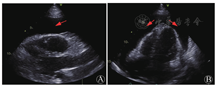

患者入院行心电图为窦性心律、律齐,肢体导联低电压表现。行胸部CT提示右侧胸腔大量积液,右肺膨胀不全,双肺散在索条、斑片、淡片影。床旁超声心动图见大量心包积液(图1),遂行心包穿刺置管引流术(经心尖入路),引流液为暗红血性液体,送检引流液常规:外观血性混浊,比重1.030,细胞总数1 852 020×106/L,白细胞总数995×106/L,单核55%,多核45%,黎氏试验阳性;引流液生化:总蛋白(TP)44 g/L,白蛋白(Alb)29 g/L,LDH 496 U/L,ADA 9.7 U/L,葡萄糖(Glu)4.7 mmol/L。同时,该引流液测得血红蛋白(Hb)69 g/L。同期外周血Hb 124 g/L,而引流后次日下降至90 g/L。引流3 d后查体发现左下肺呼吸音低,叩诊呈浊音,行胸部X线片提示左肺新发胸腔积液,未见气胸表现。

A:胸骨旁长轴平面;B:心尖四腔心平面